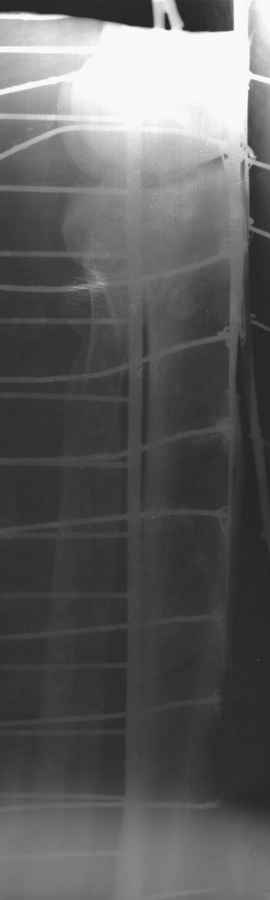

Пациенту сделали КТ - ухитрились сделать на шине Белера (не давал положить прямую ногу) - срезали передний отдел. Планируется на пятницу (24.12) на операцию - синтез длинной мыщелковой LCP-пластиной Synthes :). Отек ближе к слову умеренный (окружность голени +4 см по сравнению со здоровой). КТ и снимок на вытяжении прилагаются.

Трудно поверить, что разрекламированная Ортопедическая школа Восточной Украины позволяет такие странные снимки? На прямом снимке сохранен общий контур плато, но не известна судьба импрессии суставной поверхности. На полубоковой?, оставлен без репозиции задне-медиальный отдел, и навряд ли после такой фиксации можно удовлетвориться результатом.

Представленные снимки не информативны, нужны отдельные качественные снимки коленного сустава и голени без ротации.